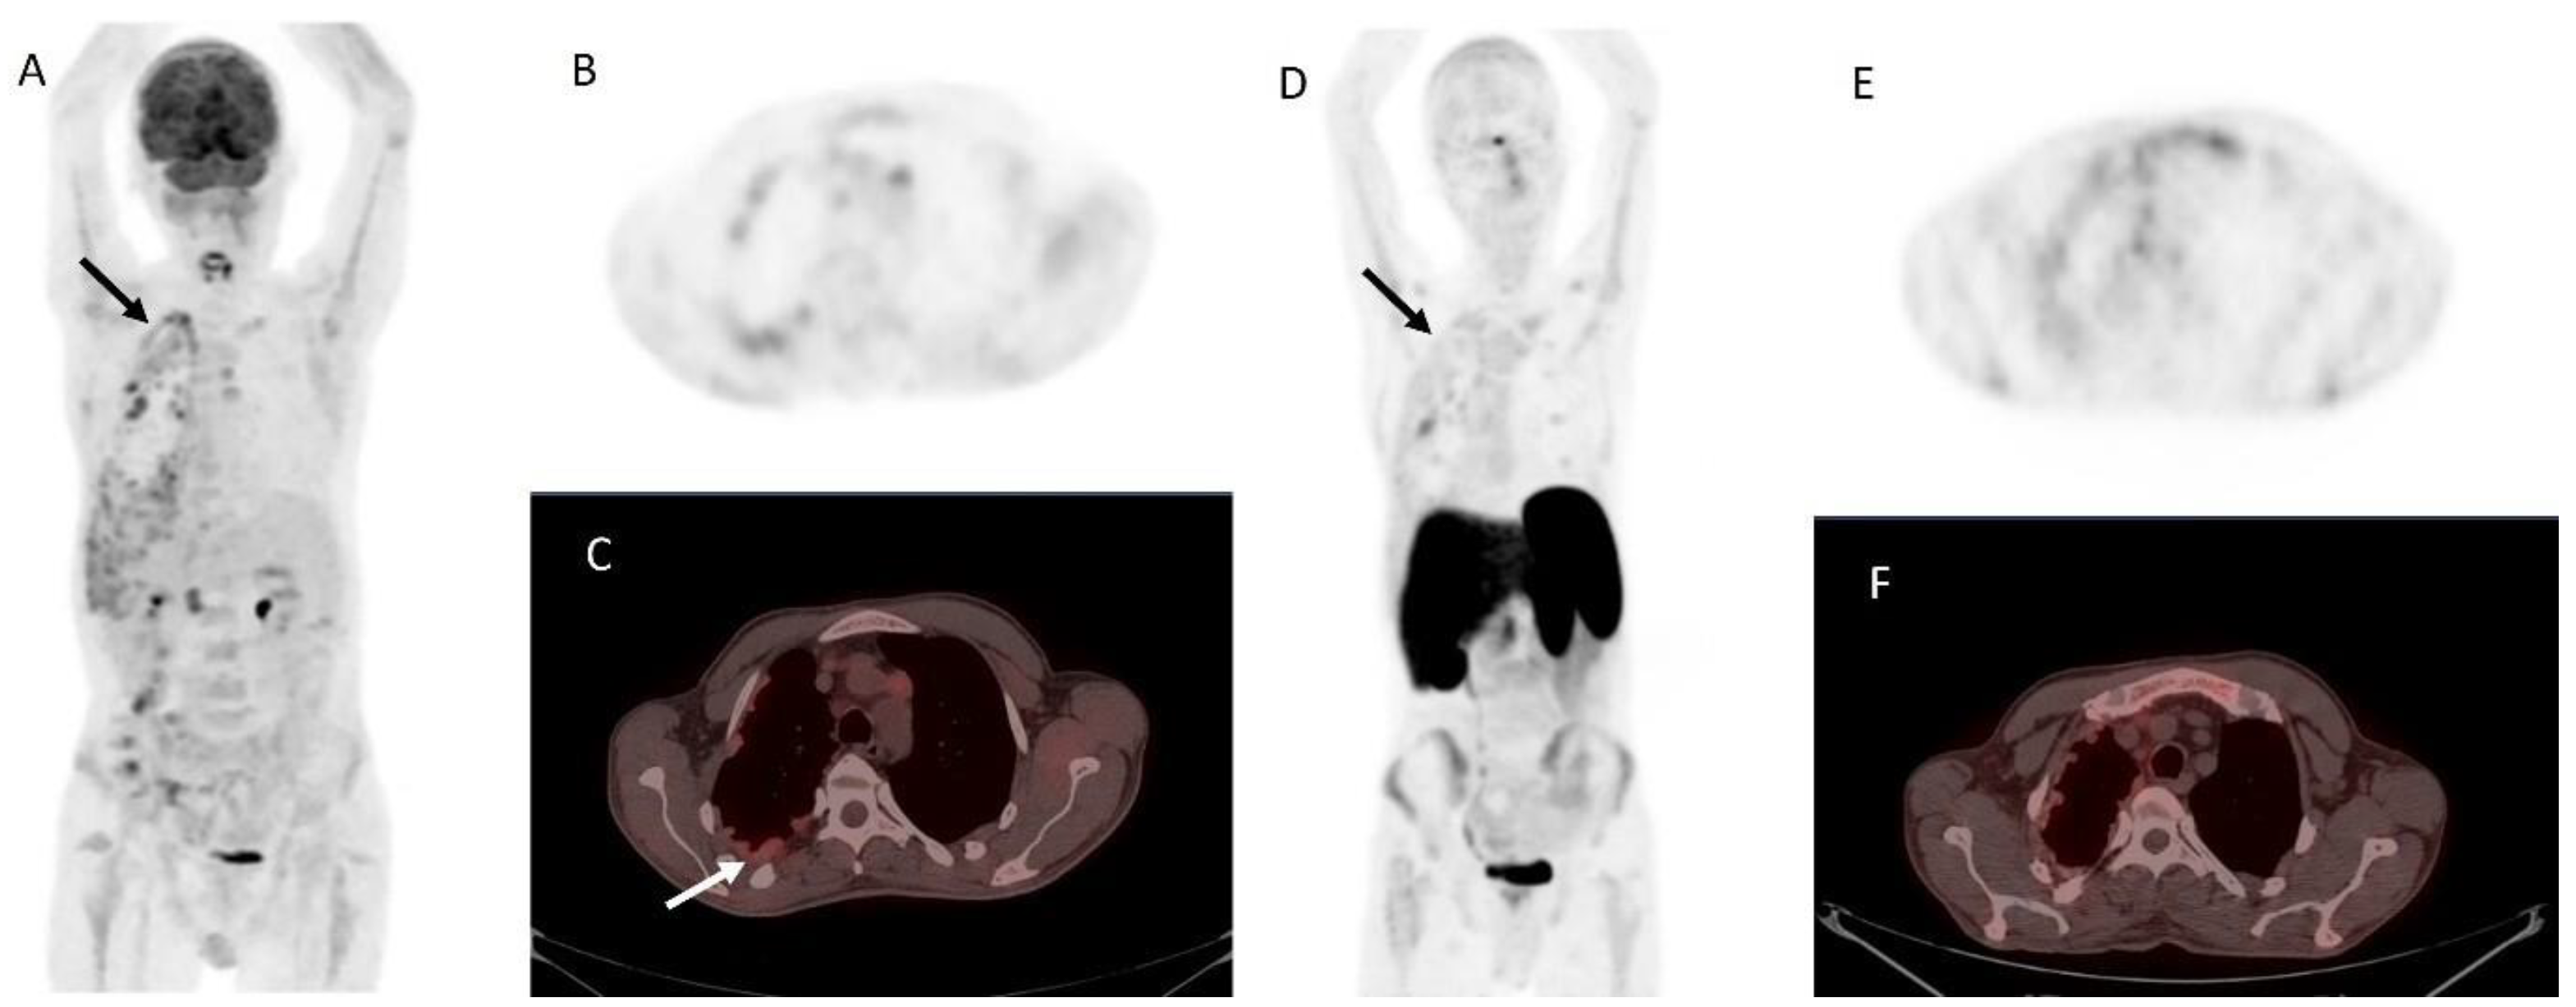

Figure 5. Metastatic parathyroid carcinoma on [18F]FDG PET/CT and [68Ga]Ga DOTA-TATE PET/CT. Legend: A 72-year-old patient with metastatic parathyroid carcinoma. He had elevated Ca levels of 13.5 mg/dL (8.8–10.6 mg/dL) and PTH levels of 11,663 (12–88 pg/mL) after repeated surgeries and tyrosine kinase inhibitor therapy. [18F]FDG PET/CT shows extensive pleural metastases ((A), whole-body MIP image, black arrow; (B), axial MIP; (C), PET/CT, white arrow). [68Ga]Ga DOTA-TATE PET/CT was acquired to evaluate options for peptide receptor radionuclide therapy ((D), whole-body MIP image; (E), axial MIP; (F), PET/CT). Unfortunately, there was a faint uptake lower than the physiological liver uptake, rendering the patient ineligible for PRRT.

However, clinical evidence remains limited. At present, SSTR imaging is not recommended as a standard diagnostic tool in PC but may be considered selectively in patients with high receptor expression where PRRT is being contemplated as a therapeutic option (Figure 6).